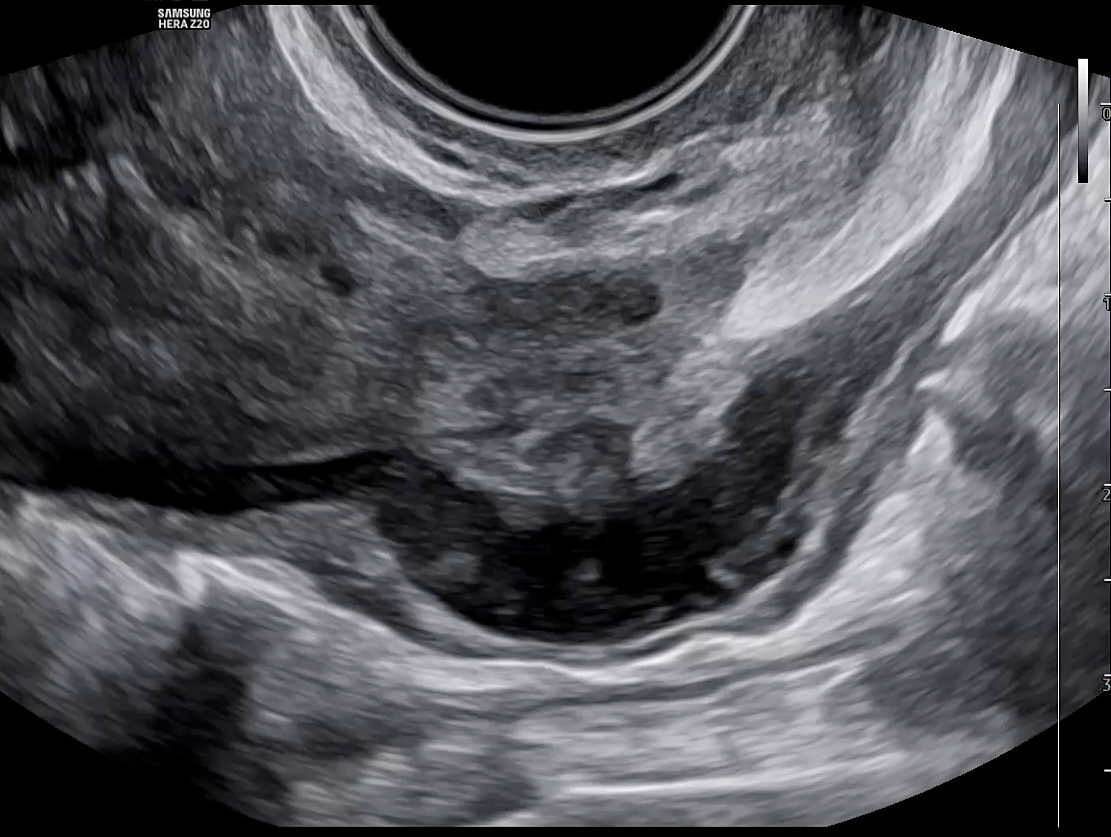

Ovarian endometriomas are associated with more extensive endometriosis, characterized by greater disease severity and the presence of multifocal DE.45 Whether or not endometriomas are present, the ovaries may appear adherent to each other and become fixed behind the uterus in the POD, a phenomenon known as ‘kissing ovaries’ sign (Figure 28). This finding points toward more severe pelvic adhesions, as well as a higher chance of bowel involvement and Fallopian tube obstruction.46

28

‘Kissing ovaries’ appearance with the left ovary attached to the uterine wall, suggestive of pelvic adhesions.